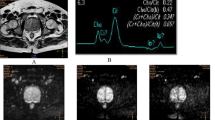

The images were processed by the ISP post-processing workstation (Philips Healthcare Co., Ltd.). Two radiologists reviewed the images independently and blindly. The maximum lesion level was selected using the T2-weighted images as the standard. Then the region of interest (ROI) was selected at the same level on the APT and DWI images to measure the APT and ADC values (Fig. 1). The averages of values measured by the two radiologists were calculated for the statistical analysis. Patients’ medical records were reviewed to obtain the total PSA (tPSA) and free PSA (FPSA).

Case examples. 1 A 75-year-old man was hospitalized, and the physical examination revealed that PSA level increased. (1A) T2WI. (1B) APT. (1C) DWI. (1D) ADC. 2 A 68-year-old man was hospitalized for treatment after finding the possibility of prostate malignancy in the external hospital. (2A) T2WI. (2B) APT. (2C) DWI. (2D) ADC

As presented in Table 4, the quantitative parameters in differentiating malignant prostate lesions from benign prostate lesions were significantly different (P < 0.05), except for APTmin (P > 0.05). Quantitative APT parameters, including APTmax and APTmean, could well distinguish malignant prostate lesions from benign prostate lesions. Comparatively, APTmax had a higher sensitivity (92.310), and APTmean had a higher specificity (77.780), while they both had high area under the curve (AUC) values (Fig. 1A and Table 5).The other parameters had relatively high values in differentiating malignant prostate lesions from benign prostate lesions. ROC curves were plotted and showed that ADCmean had the highest AUC value (0.793, 95% confidence interval (CI): 0.688–0.876), APTmax had the highest sensitivity (92.310), and FPSA had the highest specificity (100.000) (Fig. 2A, B, C and Table 5).